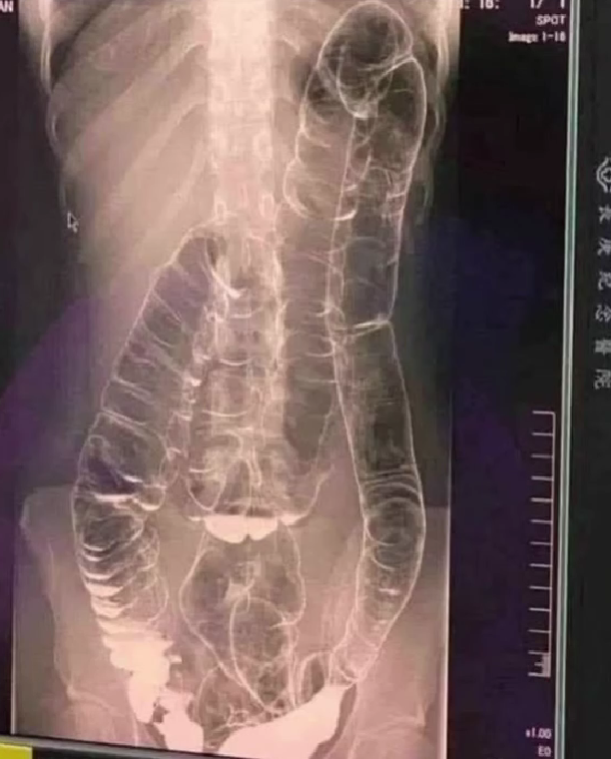

When waste accumulates in the colon due to an inefficient digestive system, it causes severe discomfort and bloating. Over time, the colon expands beyond its normal size, struggling to contain the excessive buildup of feces. In this case, medical imaging revealed a severely distended colon that had enlarged so much it reached up toward the chest, dangerously close to the heart. The stretching had nearly erased the colon’s natural folds and wrinkles, essential for its proper function. Left untreated, this condition could have led to life-threatening complications.One of the most dangerous effects of chronic constipation is severe colon distension. When the colon becomes overstretched, it loses its ability to contract properly, making bowel movements increasingly difficult. This leads to a vicious cycle in which waste remains in the body for even longer periods, further aggravating the problem.